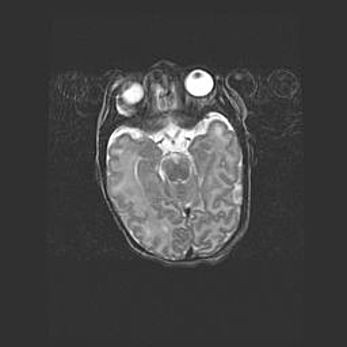

Сообщающаяся гидроцефалия. Кистозная энцефаломаляция головного мозга.

Возраст: 3 месяца 4 дня

Вес: 3100 г

Пол: женский

Окружность головы: 34 см

Срок гестации: 31 неделя

Кистозная энцефаломаляция головного мозга - одна из форм поражения головного мозга в детском возрасте. Характеризуется возникновением множественных и распространённых кист в коре, белом веществе и подкорковых образованиях головного мозга у плодов, новорождённых и детей раннего возраста. Развитие кистозной энцефаломаляции связано с внутриутробной асфиксией и гипотонией, родовой травмой, тромбозом синусов, пороками развития сосудов, инфекциями, сепсисом и другими причинами. Наиболее значимые инфекционные агенты: вирусы простого герпеса, цитомегалии, краснухи, токсоплазмы, энтеробактерии, золотистый стафилококк и другие.